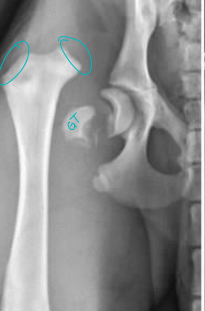

Hip

Effusion: rarely palpable

Ortolani maneuver (hip laxity; done under sedation)

Lumbosacral vs Hip Pain

Palpation: compression test

Standing exam: Take weight off legs, lateral

extension of limbs: iliopsoas pain (tightens w/ age)

Raise tail: flexes hip joint

Rectal exam: pressure dorsal to joint